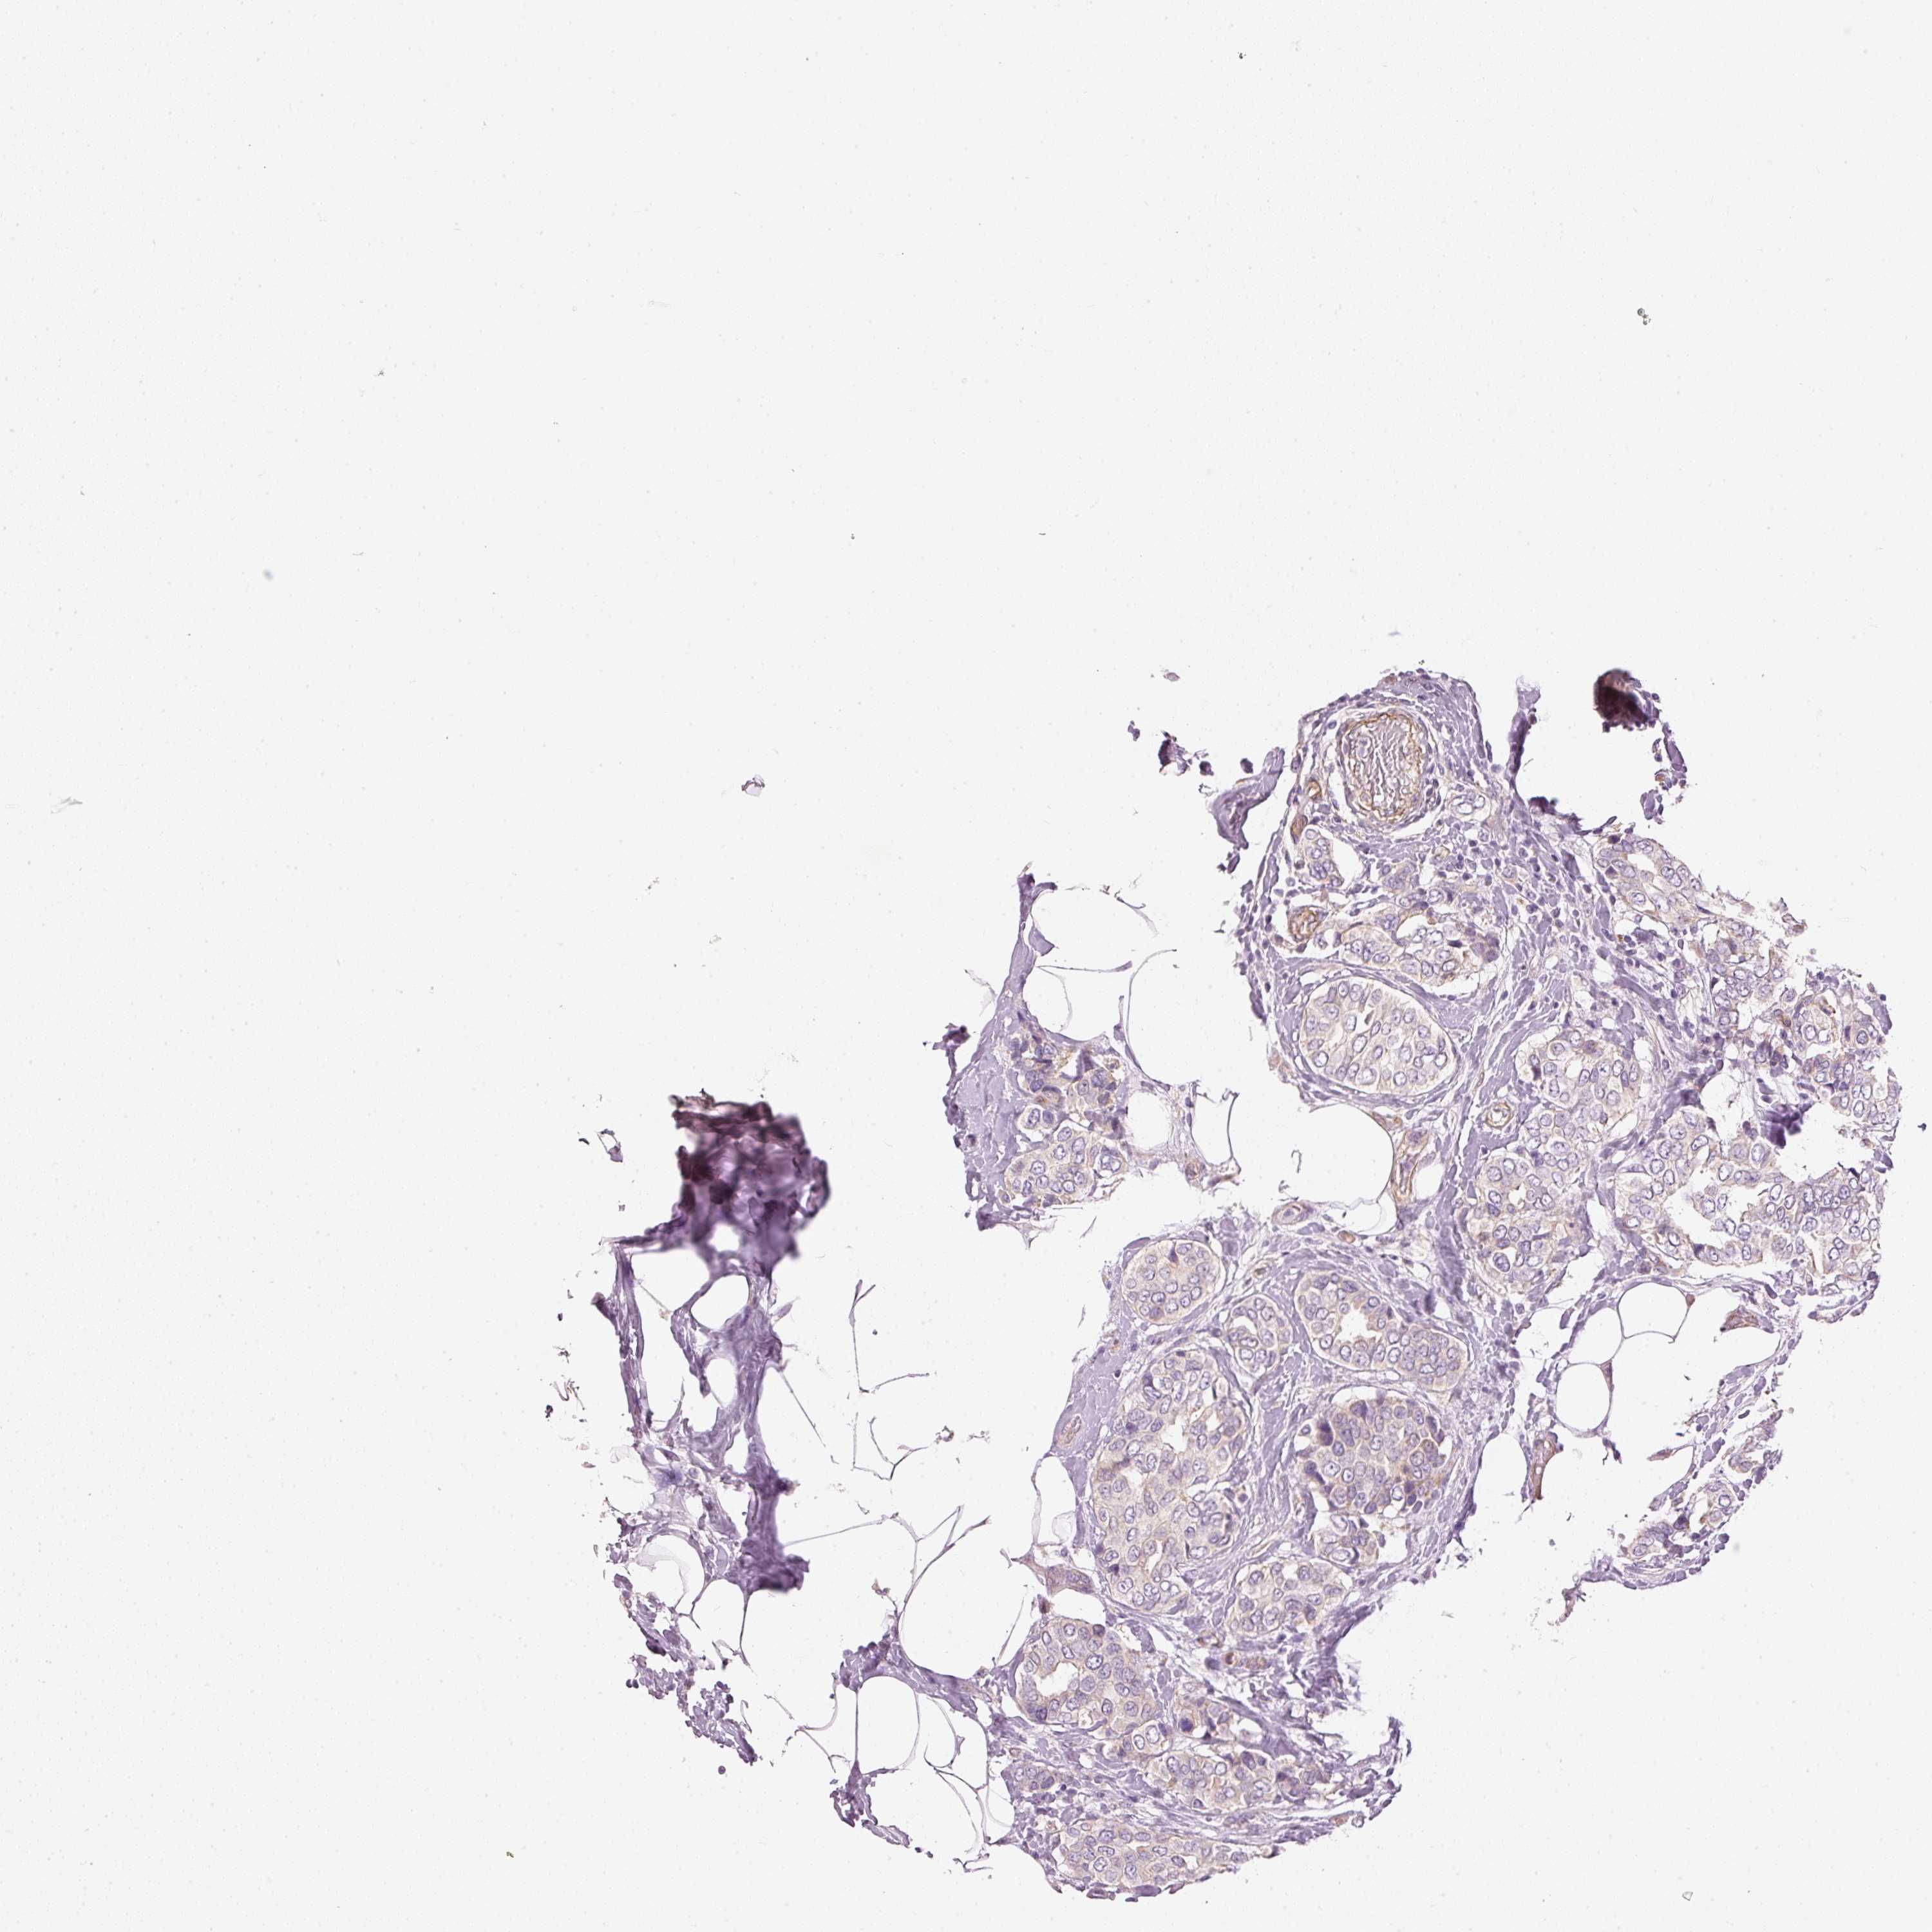

CANCER BREAST CANCER Show tissue menu

Breast cancer

Human cancer